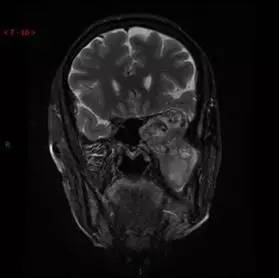

T2WI/FS冠状位

DWI